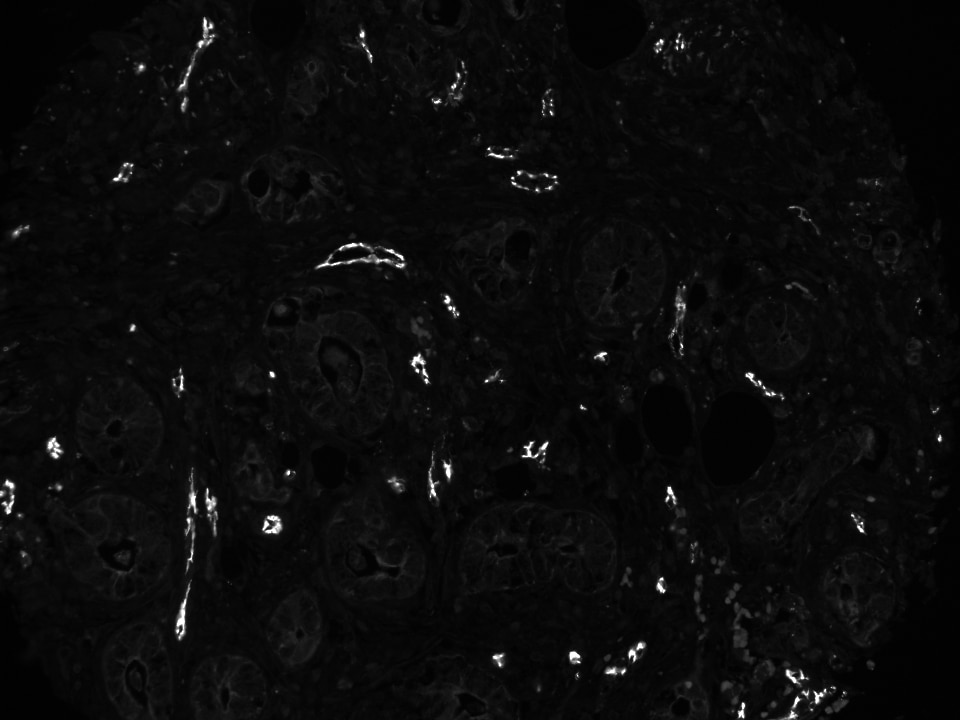

Amazon.com : Kenko PL Filter ZX Circular 77 mm high, CD31/PECAM-1 Antibody (C31.3 + C31.7 + C31.10) - Azide and,